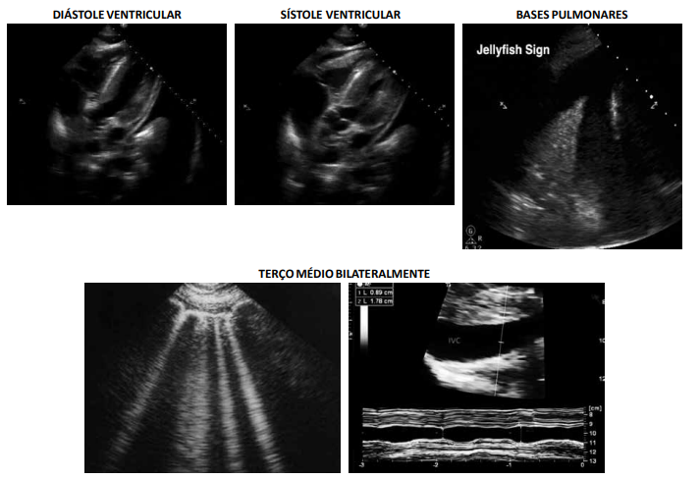

Considere-se que, após o manejo inicial, foi realizado POCUS, obtendo-se as imagens cardíacas, de veia cava e pulmonar a seguir.

Com base na situação hipotética apresentada e nas imagens resultantes da realização do POCUS, assinale a alternativa correta.